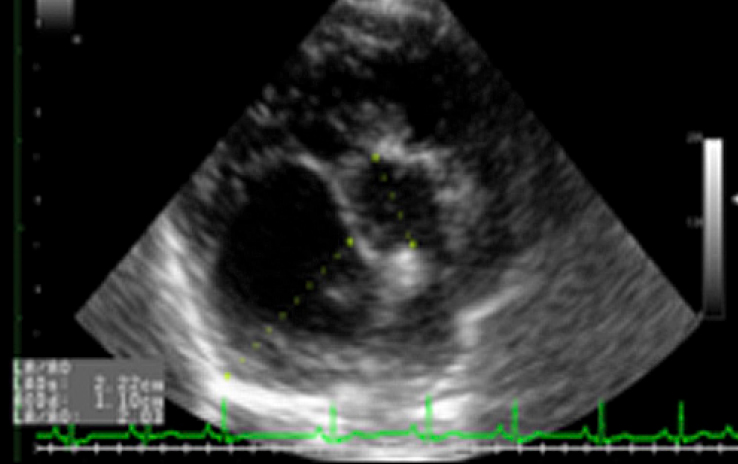

超音波検査

心臓の超音波検査をすることで、心臓の弁の動きや心臓の各部屋の大きさ、筋肉の厚さなど心臓の内部まで詳細に把握する事が可能です。また、心臓内を流れる血液の早さを測る事で、心臓の機能の厳密なモニターが可能です。心臓の何処がどのように大きくなっているのか、血液の流れはどうなのか、はっきりと把握することが、適した治療につながります。

LA/AO

左心房と大動脈の大きさの比較。

心臓の拡大の程度を探ります。

カラードプラ

血液の流れる向きを色で示し、逆流やジェットを明らかにします。

肥大型心筋症(HCM:Hypertrophic Cardiomyopathy)

犬より猫での発生が多い心臓の病気です。心臓の筋肉が肥大し、循環不全を起こす病気です。症状としては、発咳、運動不耐性、または開口呼吸などがみられます。また、負担がかかって拡張した左心房内に血栓が生じ、これが全身に流れ出て様々な血管を詰まらせる「血栓塞栓症」という緊急疾患を起こすリスクを伴います。血栓が心臓、脳、腎臓など様々な臓器につまって臓器の機能を急激に損なわせる事もあれば、後肢の血管につまって急に後ろ足が立たなくなる事もあります。猫種の中でもメインクーンやアメリカンショートヘアでの発生が多くみられるため注意が必要です。この病気は初期には非常に気づき難いため、メインクーンやアメリカンショートヘアの子では特に健康診断など定期的な検査を行う事をお勧めしています。

疾患が疑われる場合にはX線検査や超音波検査を行います。胸部X線検査では心臓の形や大きさの変化、超音波検査では筋肉の厚さや内腔の広さなどを評価します。